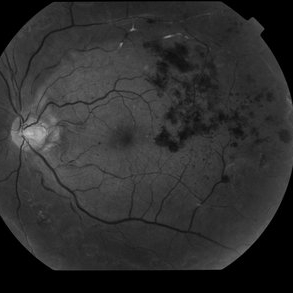

Proliferative Diabetic Retinopathy with Subhyaloid Hemorrhage

Oct 18 2012 by Suber S. Huang, MD, MBA, FASRS

43-year-old diabetic man with proliferative diabetic retinopahty, subhyaloid hemorrhage, ischemia, neovascuarization.

Photographer: Stacie Hrvatin

Condition/keywords: ischemia, retinal neovascularization, subhyaloid hemorrhage